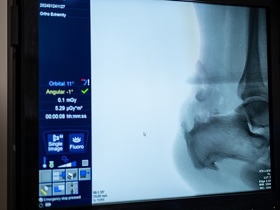

Магнітно-резонансна томографія (МРТ) стопи ― це безпечний високоточний метод діагностики, який призначають ортопеди-травматологи, ревматологи, онкологи, неврологи та хірурги. Завдяки йому можлива чітка візуалізація внутрішніх структур та тканин всіх відділів стопи (кісток, суглобів, зв’язок, кровоносних судин, нервів). Розшифровка зображень МРТ допомагає виявити патологічні зміни та встановити точний діагноз.

Дистальні відділи ― це кінцева (нижня або передня) частина стопи, до якої відносять плеснові кістки, міжфалангові суглоби та фаланги пальців ніг.